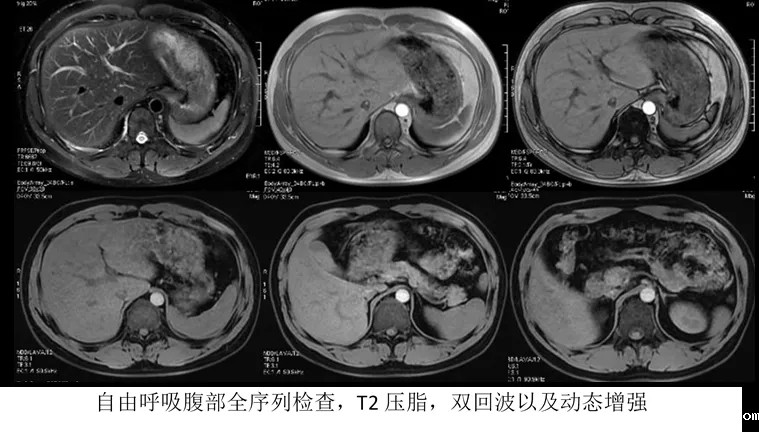

在SIGNA Creator智简平台上,我们可以通过自由呼吸的方式进行腹部全序列的检查,如图中所示,病人在自由呼吸状态下首先完成了常规T2压脂以及双回波的形态检查。随后在保持同样的状态,完成了全肝的动态增强检查。对于对于腹部动态增强检查而言,时间窗极短,在1分钟的时间内以自由呼吸的方式完成3期全肝的扫描需要极快速度采集速度以及高度的伪影抑制能力。

另外对于临床中常见的病人吞咽动作伪影,图像视野外组织的卷褶伪影干扰,组织交界处的模糊伪影以及线性伪影等,智简平台都可以进行有效的伪影抑制,提升20%的扫描成功率,进而提升成像效率。